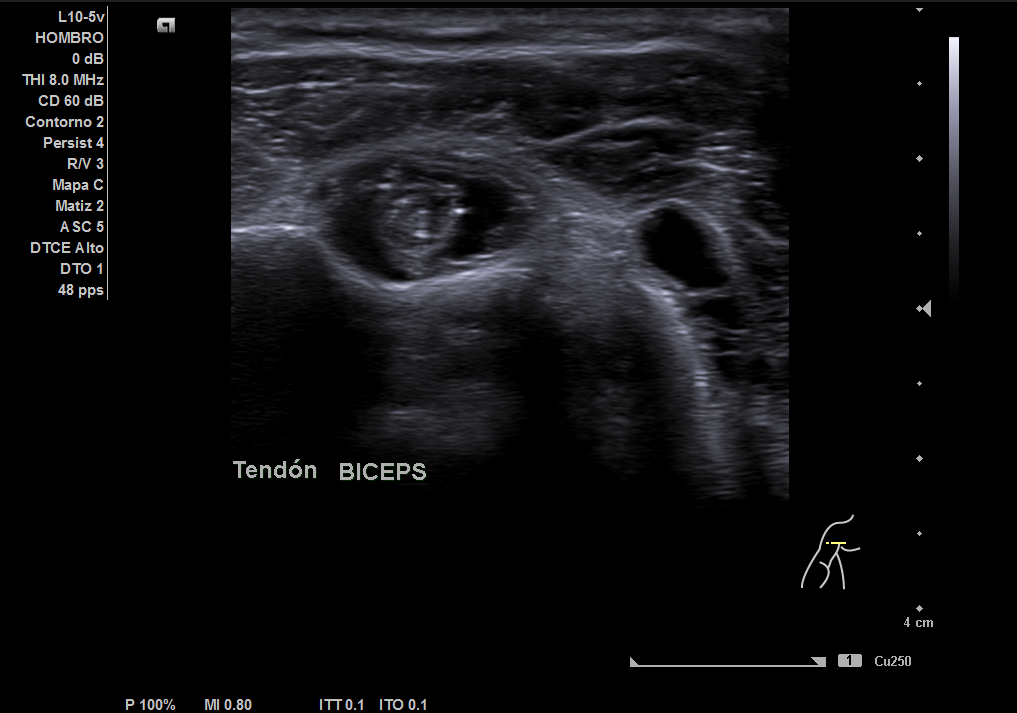

En la ecografía realizada observamos una rotura completa del tendón supraespino, rotura parcial del subescapular y severo derrame peritendón del bíceps junto con derrame articular glenohumeral.

Juicio diagnóstico: rotura manguito de los rotadores (rotura completa supraespinoso).